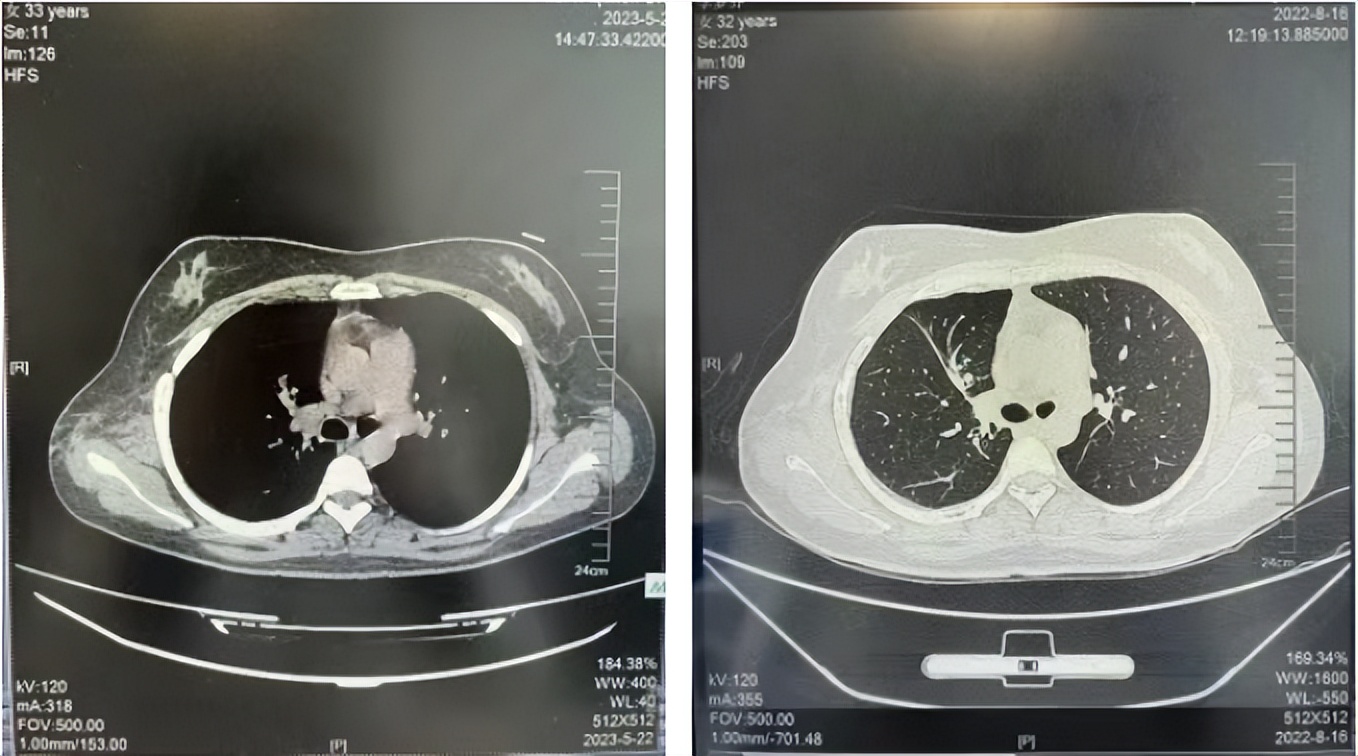

2016年1月复查CT提示支气管截断可见新发小结节,一线治疗采用培美曲塞+DDP方案化疗4周期(培美曲塞3.36,DDP 480mg)。化疗后复查胸部CT:右肺见不规则结节样影,最大层面大小约19mm*8mm,较前比较明显增大,疗效评估PD。2017.3-2017.4予单药多西他赛化疗3周期,疗效评估SD。2018年5月末复查CT提示结节较前增大,评效为PD,2018年6-10月予多西他赛+CBP化疗4周期,疗效评估SD。2022年5月患者出现活动后气短,复查胸部CT示右肺膨胀不良;右侧胸腔积液增多。胸腔积液包埋病理示符合肺腺癌细胞。行NGS基因检测:EML4:exon13-ALK:exon20融合。PD-L1(克隆号22C3)TPS<1%。

临床诊断:右肺上叶恶性肿瘤rT0N0M1a IVA期(第9版分期);恶性胸腔积液。

诊疗经过:2022年5月始口服克唑替尼3个月,出现肝功能异常(DILI 2级伴临床症状),改用恩沙替尼靶向治疗至今,目前评效为维持PR。恩沙替尼应用期间出现轻度肝功能异常(DILI 1级),对症处理后好转。截止目前PFS 33个月。

2023.05